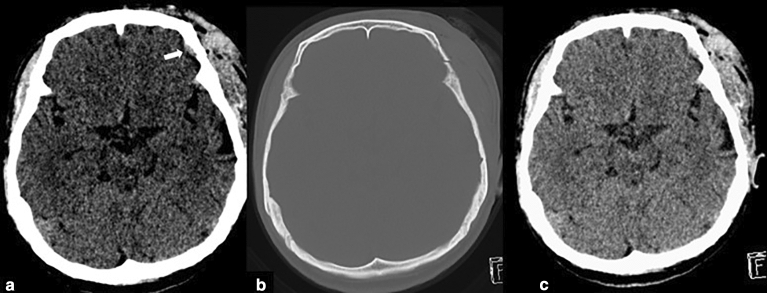

In several cases, the deep learning model detected subtle SDH when this could not be detected by any of the residents. Most of these cases were studies containing thin SDHs either along the tentorium cerebelli or the cerebral convexities. Some of these cases had various hemorrhagic subtypes resulting in small hemorrhages being overlooked. Three subtle EDHs were missed by radiology residents, and five subtle EDHs were missed by non-radiology residents. However, all of these EDHs were picked up by the algorithm. These cases are illustrated in Figs. 4 and 5. Only two cases of small EDHs were missed by the deep learning but were able to be detected by all residents (Fig. 6).

Figure 6.

The CT scan of the brain shows a small left frontal convexity EDH (white arrow) in narrowed window setting (a) and associated skull fracture in the bone window setting (b). The post-processing image reveals that the EDH has not been annotated by the algorithm c).